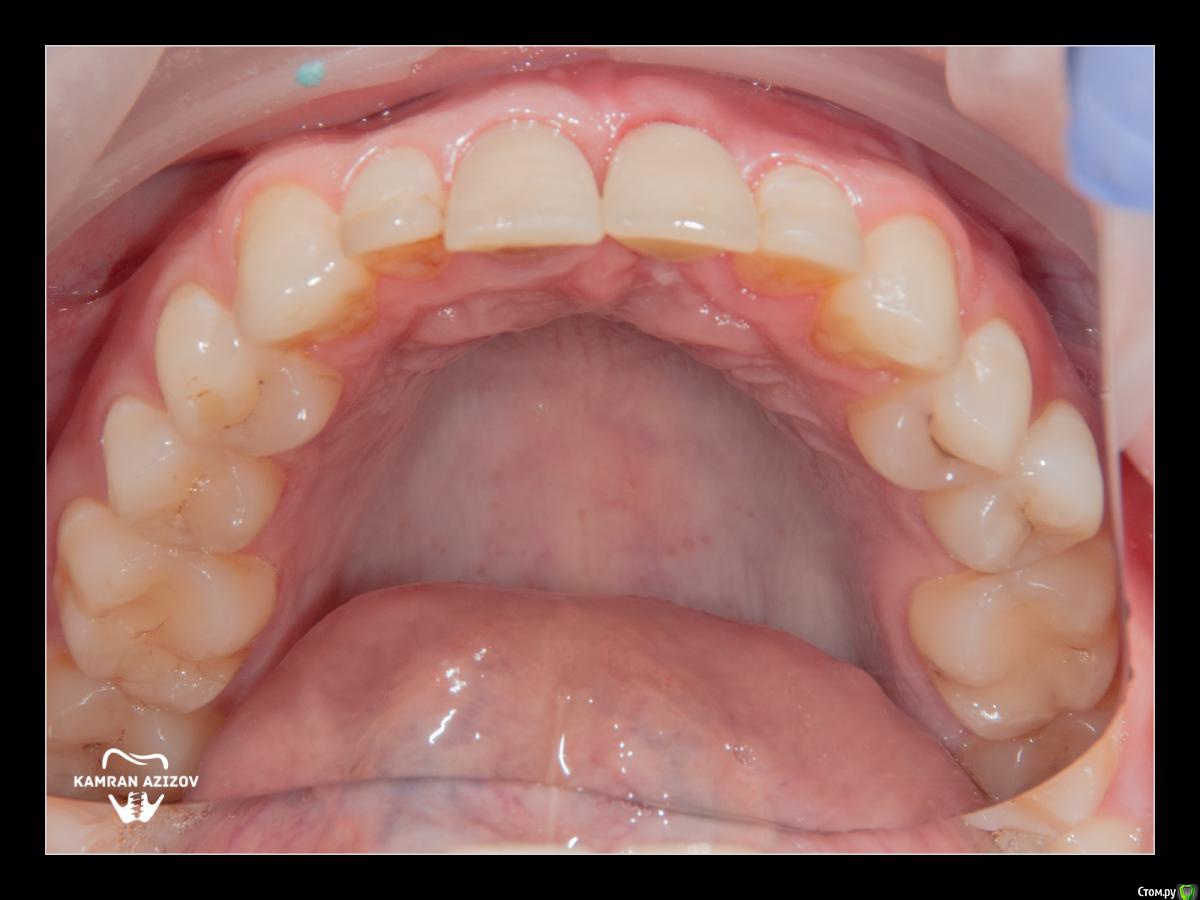

kamranchick Опубликовано 8 октября, 2019 Поделиться Опубликовано 8 октября, 2019 удаление зуба+консервация лунки с вестибулярным ССТчерез 2 месяца имплантация с фдм по карлоссучерез 4 месяца замена на более длинный фдм и широкийпостоянная коронка 5 Ссылка на комментарий

Nazim_NV86 Опубликовано 10 октября, 2019 Поделиться Опубликовано 10 октября, 2019 посмотрел только последнюю фотку. Такая зпкд всё прощает Ссылка на комментарий